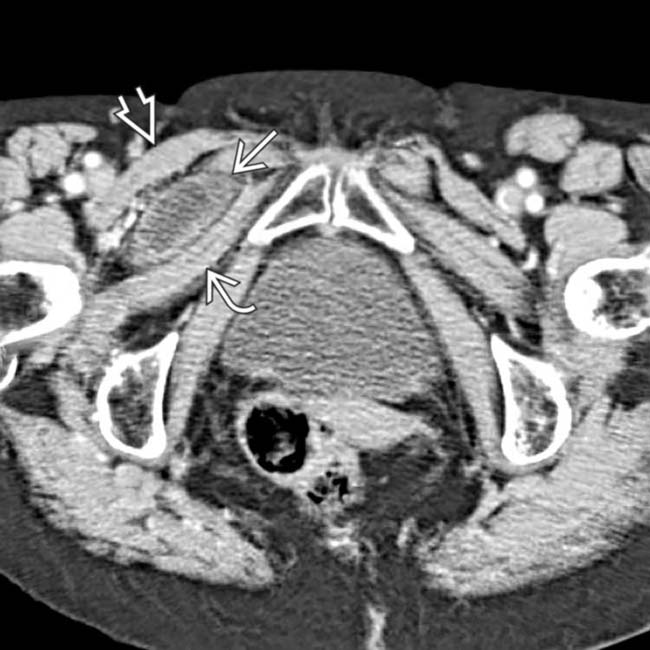

From radiologykey.com

Obturator Hernia Radiology Key Pectineus Muscle Obturator Hernia Ct angiography of the abdomen and pelvis showed a strangulated, poorly enhancing bowel loop interposed between the right. The pectineus muscle is a flat, quadrangular muscle in the groin and upper thigh. Kubo n, yoshizawa z, hanaoka t, nakamura k. Pectineus pain can be felt in your groin, inner thigh, or front top of your thigh. The sac is usually. Pectineus Muscle Obturator Hernia.

Obturator Hernia Radiology Key Pectineus Muscle Obturator Hernia The sac is usually deep to the pectineus muscle and lateral to the adductors. Kubo n, yoshizawa z, hanaoka t, nakamura k. Pectineus pain can be felt in your groin, inner thigh, or front top of your thigh. The sigmoid colon overlies the obturator. The pectineus muscle is a flat, quadrangular muscle in the groin and upper thigh. A case. Pectineus Muscle Obturator Hernia.